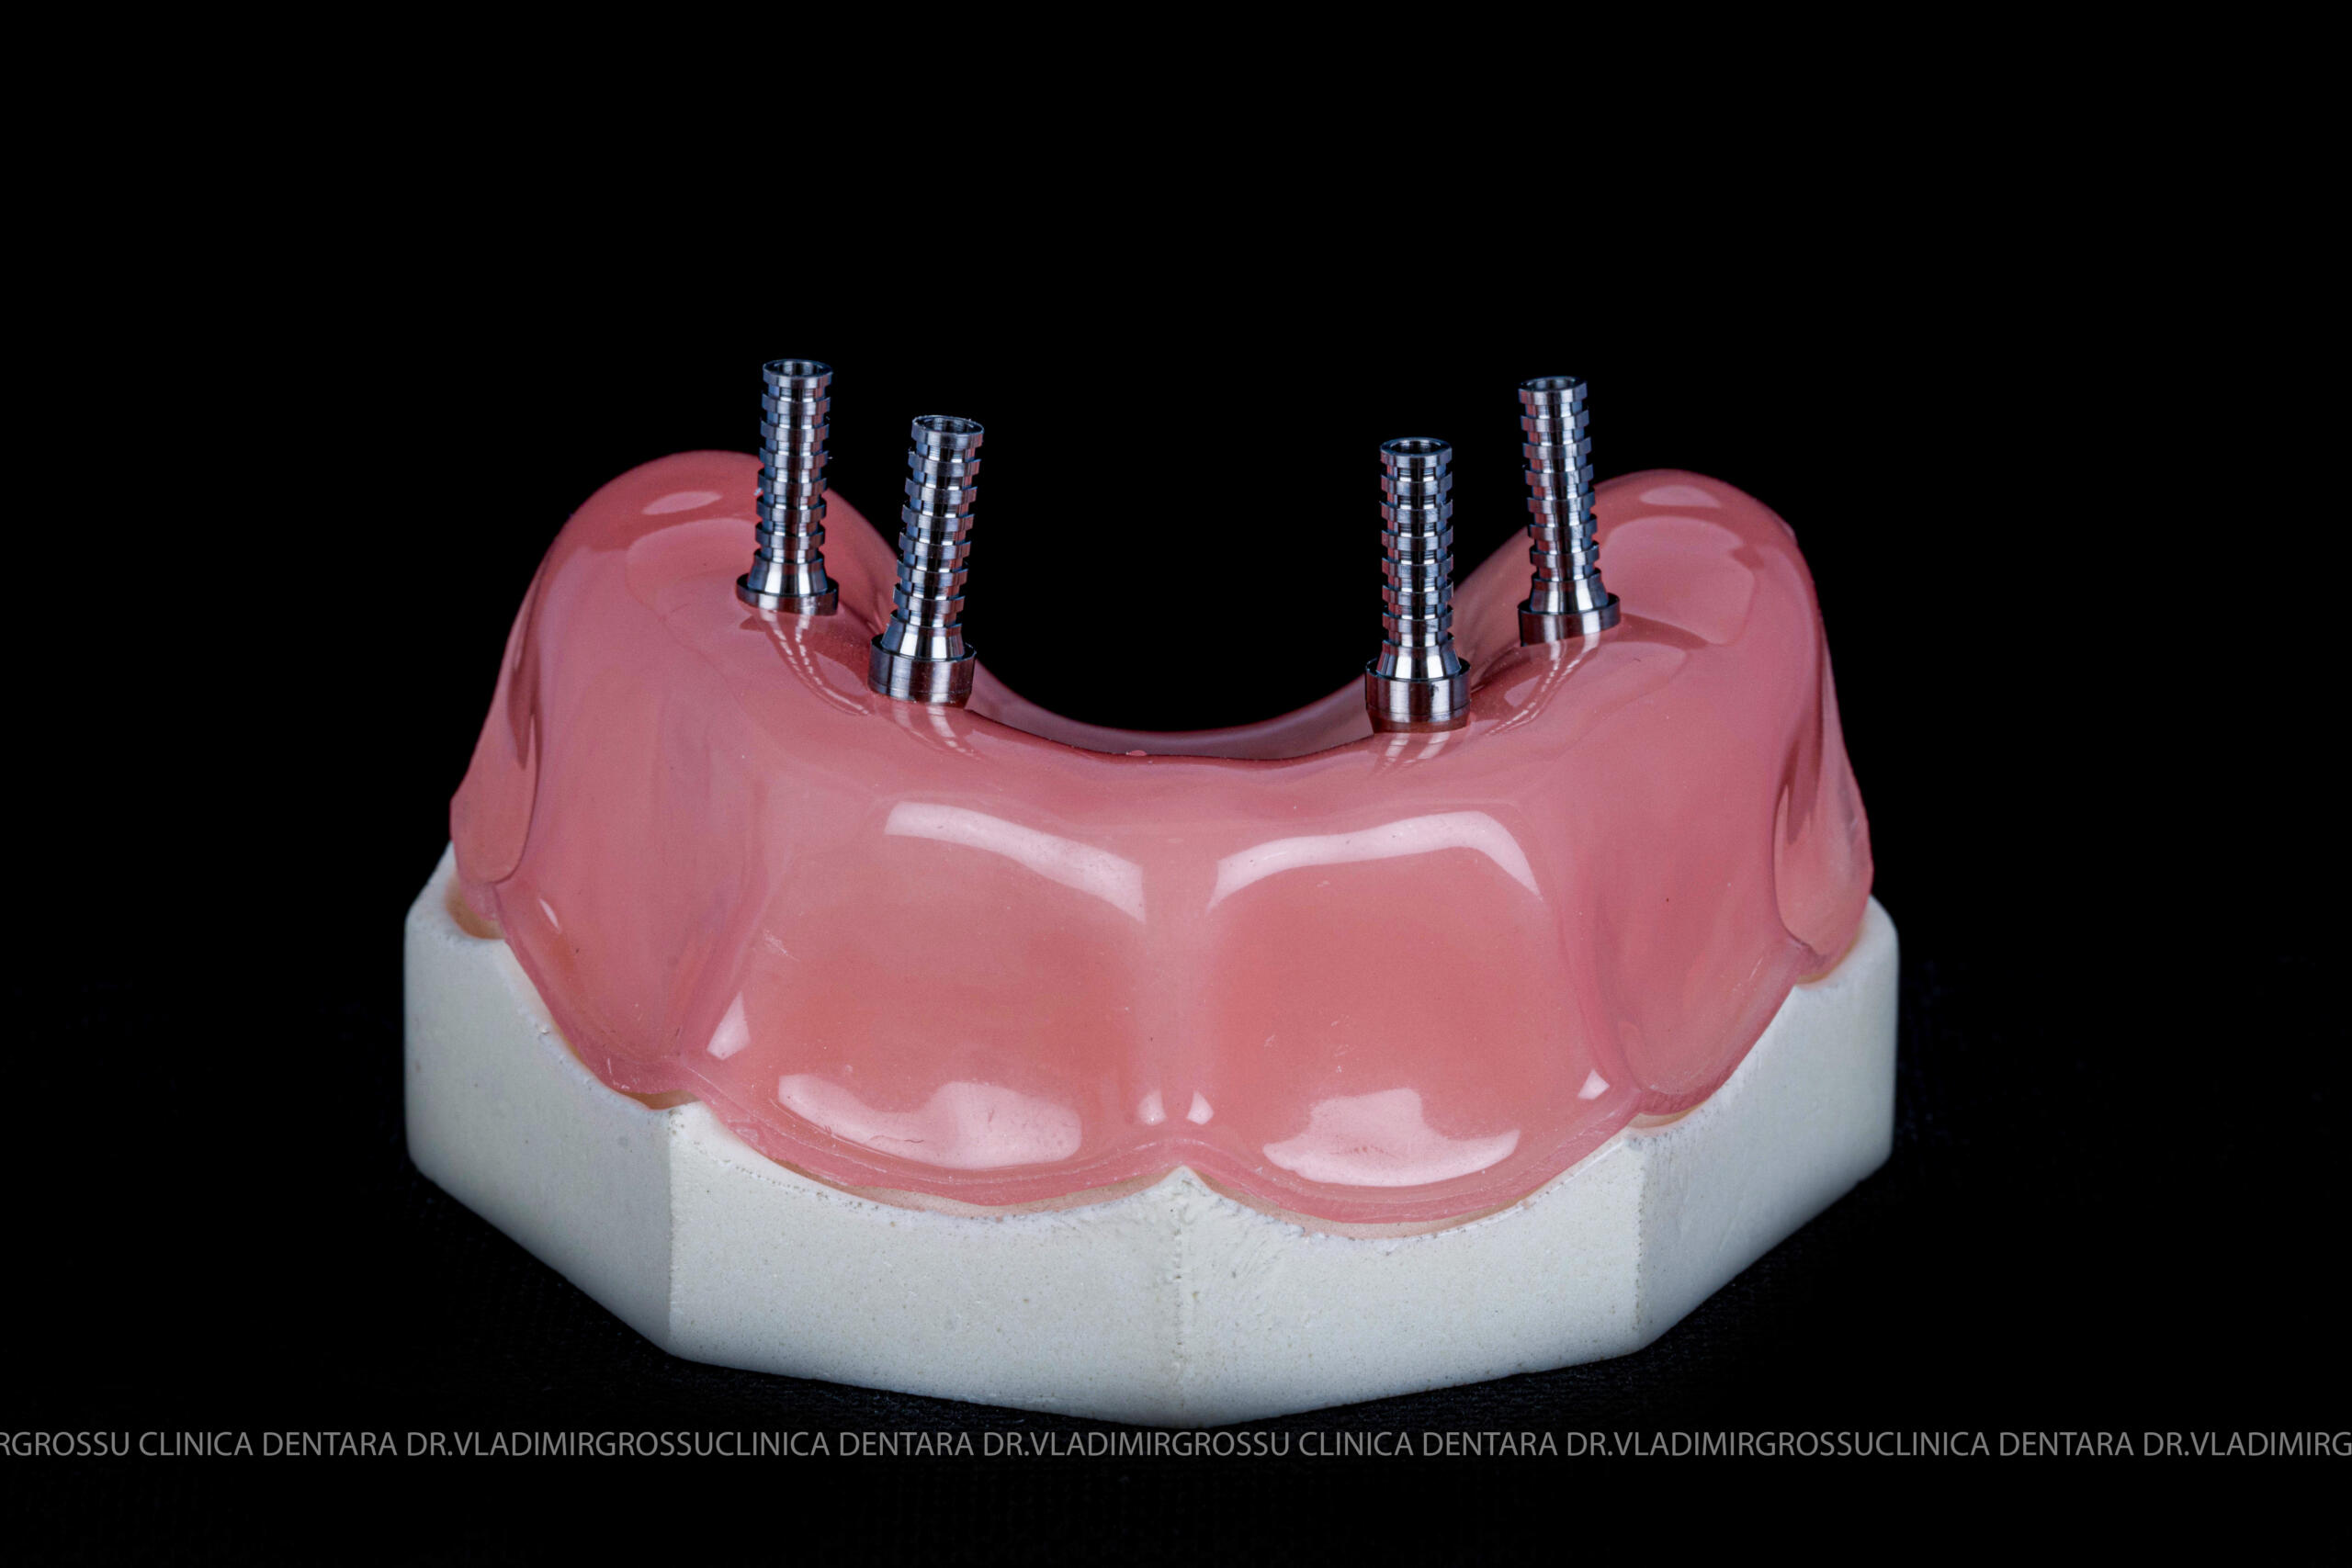

Etapa provizorie:

- 4 implanturi;

- 2 multiunit-uri drepte și 2 multiunit-uri angulate, conform necesităților protetice;

- 4 abutment-uri provizorii pe multiunit-uri;

- Proteză provizorie din masă plastică frezată sau proteză mobilizabilă pregătită și ajustată la componentele protetice.